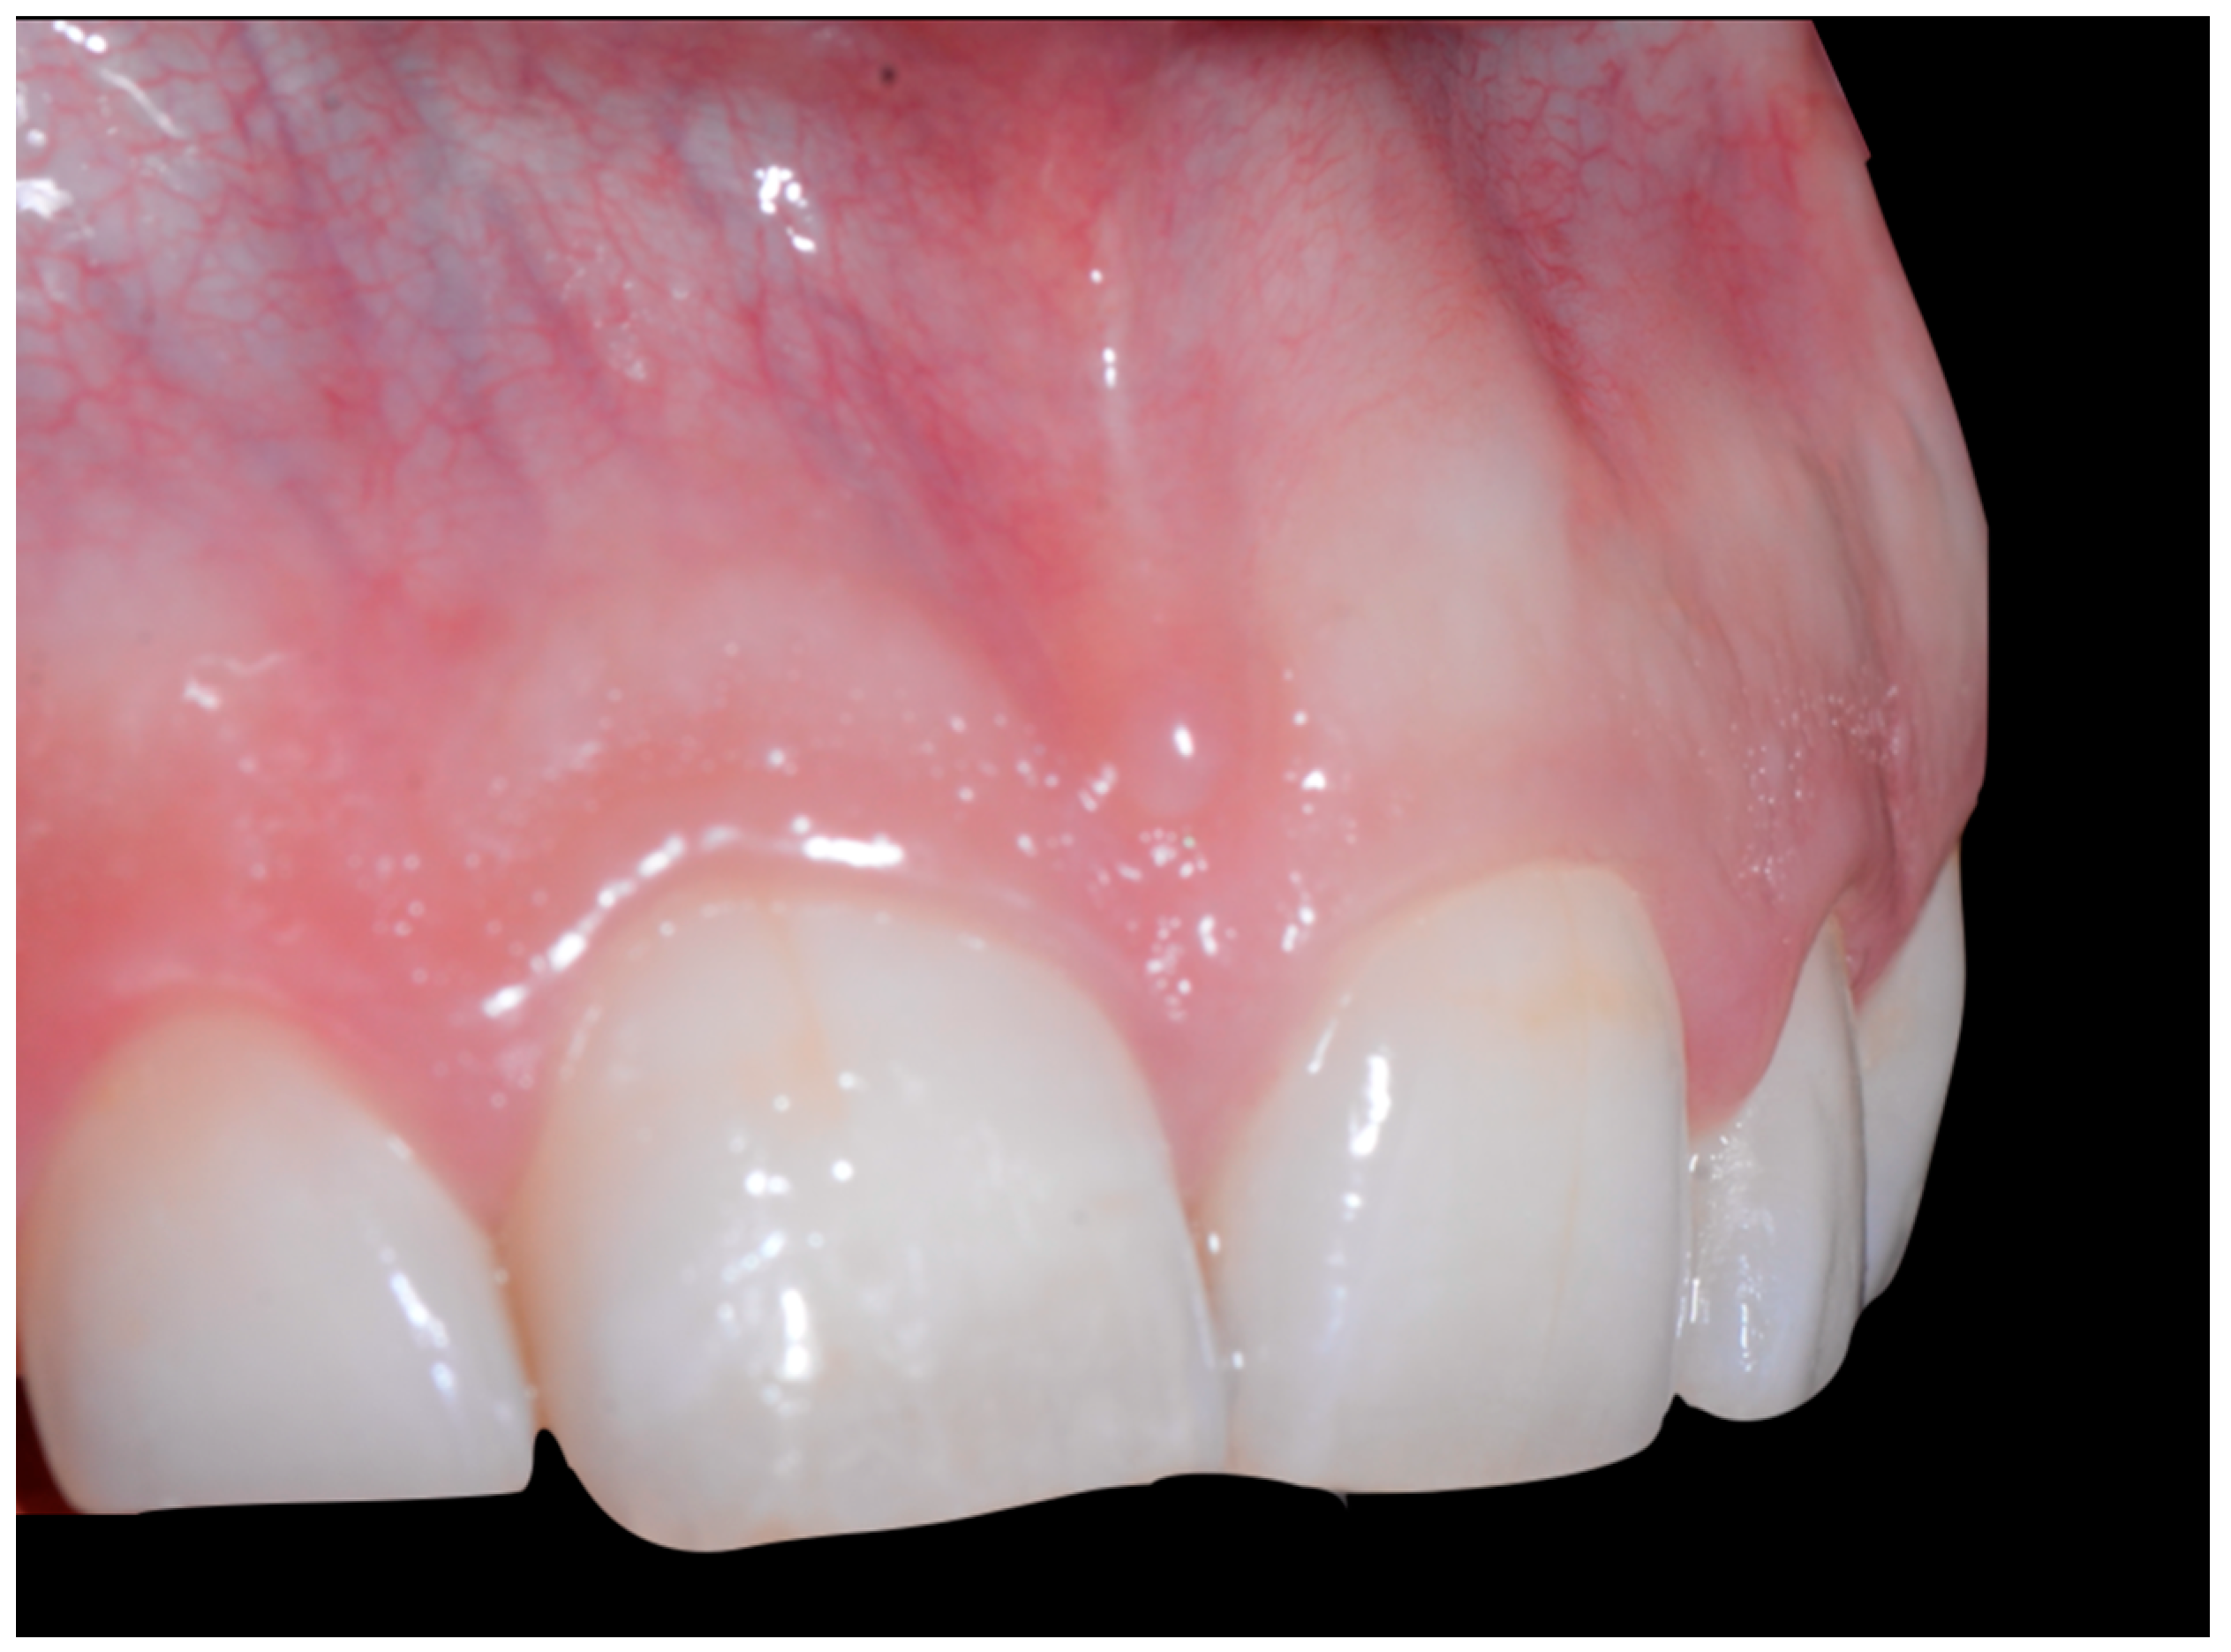

A 40-year-old patient presented with discomfort in tooth 31, citing past orthodontic treatment. As shown in Figure 11, the patient was in Class I and had poor oral hygiene associated with the presence of calculus in the incisivo-canine region. The root of 31, visible to its apex, was out of the bone and associated with severe gingival recession (Cairo RT2). Teeth 41 and 42 also showed gingival recession (Cairo RT2 and RT1).

Severe wire syndrome. Frontal and lateral views.

Figure 12 and Figure 13 show a difference in the height of the free edges of the mandibular incisors and the extent of root visibility of 31.

Severe wire syndrome. Frontal view.

Severe wire syndrome. Lateral views.